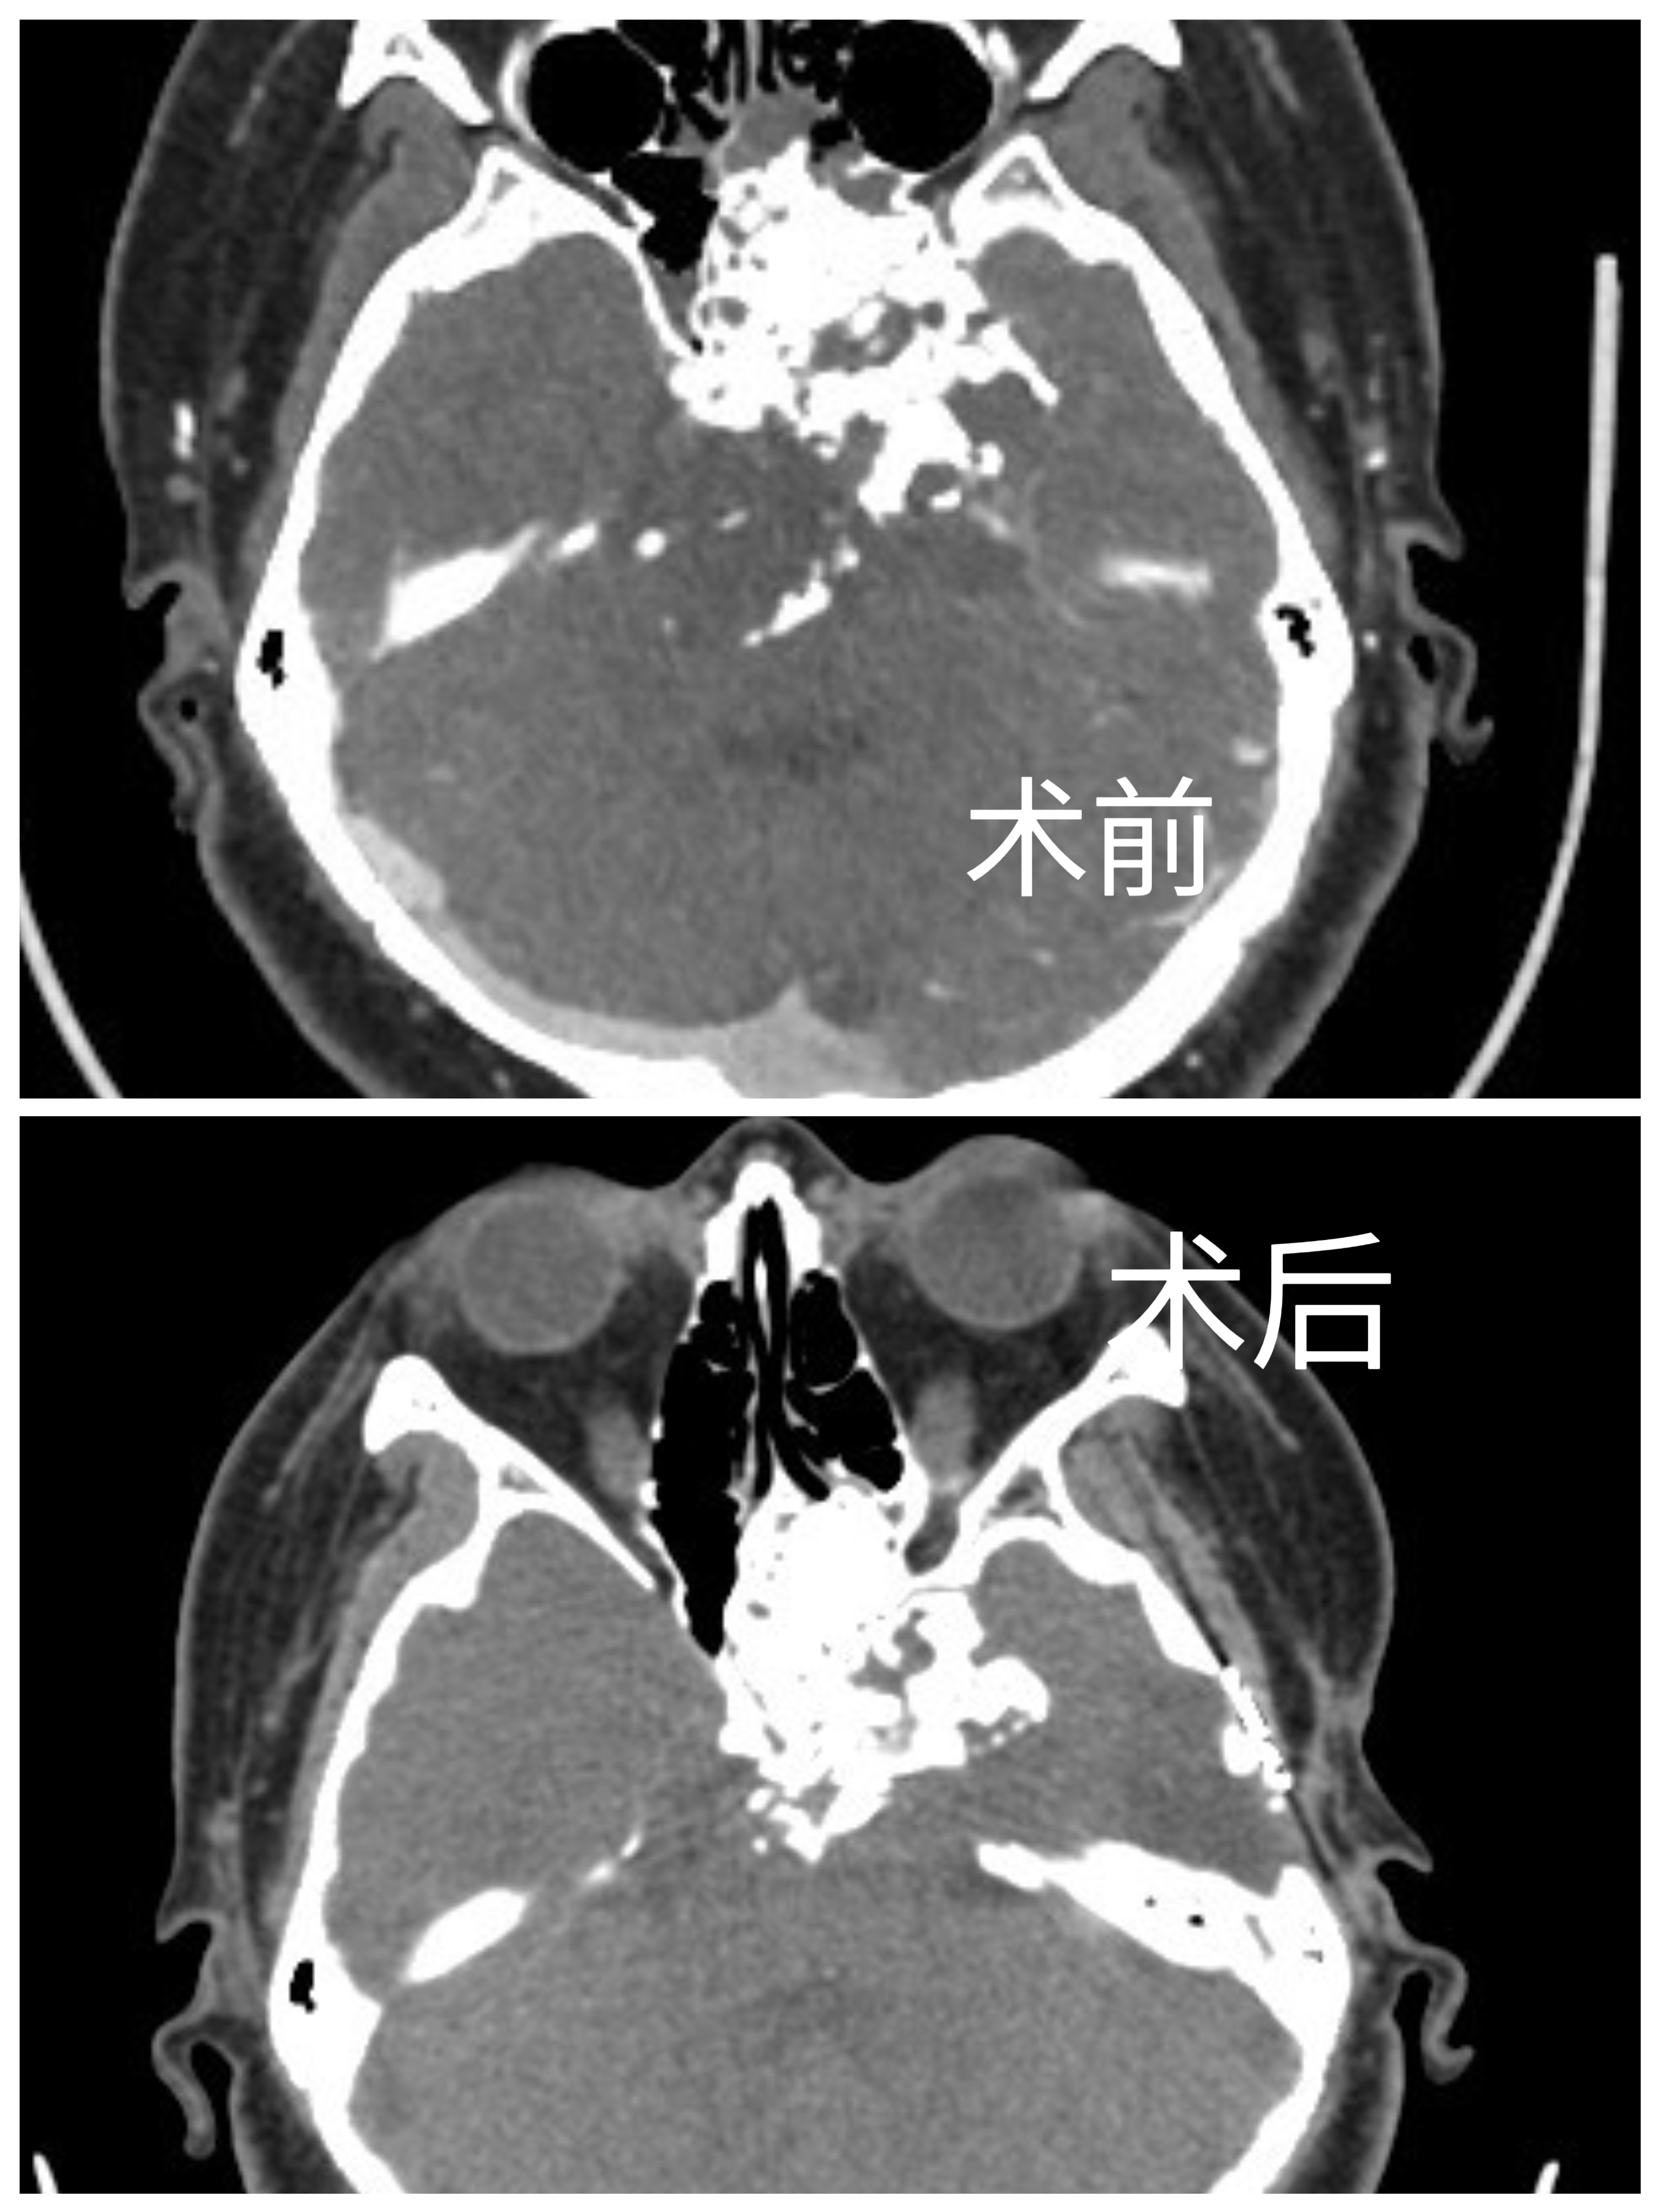

手术前

手术后